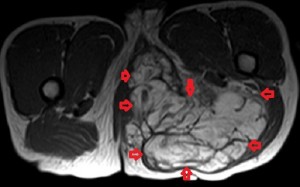

All the images in the lower panel are MR images (from left to right, axial unenhanced T1; fat-suppressed T1 post-gadolinium; coronal T1 without fat suppression; fat-suppressed sagittal T2). They show the extent of the disease better than CT and confirm that it is primarily lipomatous with little soft-tissue content. It infiltrates most of the left gluteal muscles, occupies the entire left perineum and ischiorectal fossa, and extends proximally in the retroperitoneum to the level of the sacral promontory.